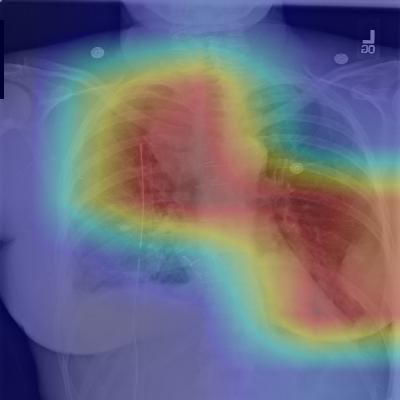

Figure 2: CheXNet localizes pathologies it identifies using Class Activation Maps, which highlight the areas of the X-ray that are most important for making a particular pathology classification. The captions for each image are provided by one of the practicing radiologists.

6 Model Interpretation

To interpret the network predictions, we also produce heatmaps to visualize the areas of the image most indicative of the disease using class activation mappings (CAMs) (Zhou et al., 2016). To generate the CAMs, we feed an image into the fully trained network and extract the feature maps that are output by the final convolutional layer. Let fksubscript𝑓𝑘f_{k} be the k𝑘kth feature map and let wc,ksubscript𝑤𝑐𝑘w_{c,k} be the weight in the final classification layer for feature map k𝑘k leading to pathology c𝑐c. We obtain a map Mcsubscript𝑀𝑐M_{c} of the most salient features used in classifying the image as having pathology c𝑐c by taking the weighted sum of the feature maps using their associated weights. Formally,

Mc=kwc,kfk.subscript𝑀𝑐subscript𝑘subscript𝑤𝑐𝑘subscript𝑓𝑘M_{c}=\sum_{k}w_{c,k}f_{k}.

We identify the most important features used by the model in its prediction of the pathology c𝑐c by upscaling the map Mcsubscript𝑀𝑐M_{c} to the dimensions of the image and overlaying the image.

Figure 2 shows several examples of CAMs on the pneumonia detection task as well as the 14-class pathology classification task.